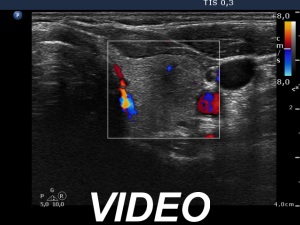

Follow-up 5 years later (3rd row of images):

Clinical presentation: Six months after the previous visit the patient became pregnant. The TSH was 5.91 mIU/L at the 5th gestational weeks. Replacement therapy was given which was ceased after delivery. The patient was free of complaints and the TSH was in the normal range, even during a next pregnancy 2 years later. Recently, a few weeks after COVID-19 infection, she noticed tenderness in the right side of the neck.

Palpation: no abnormality.

Laboratory tests: TSH 1.72 mIU/L, CRP 3.5 mg/L.

Ultrasonography: The thyroid was intact.